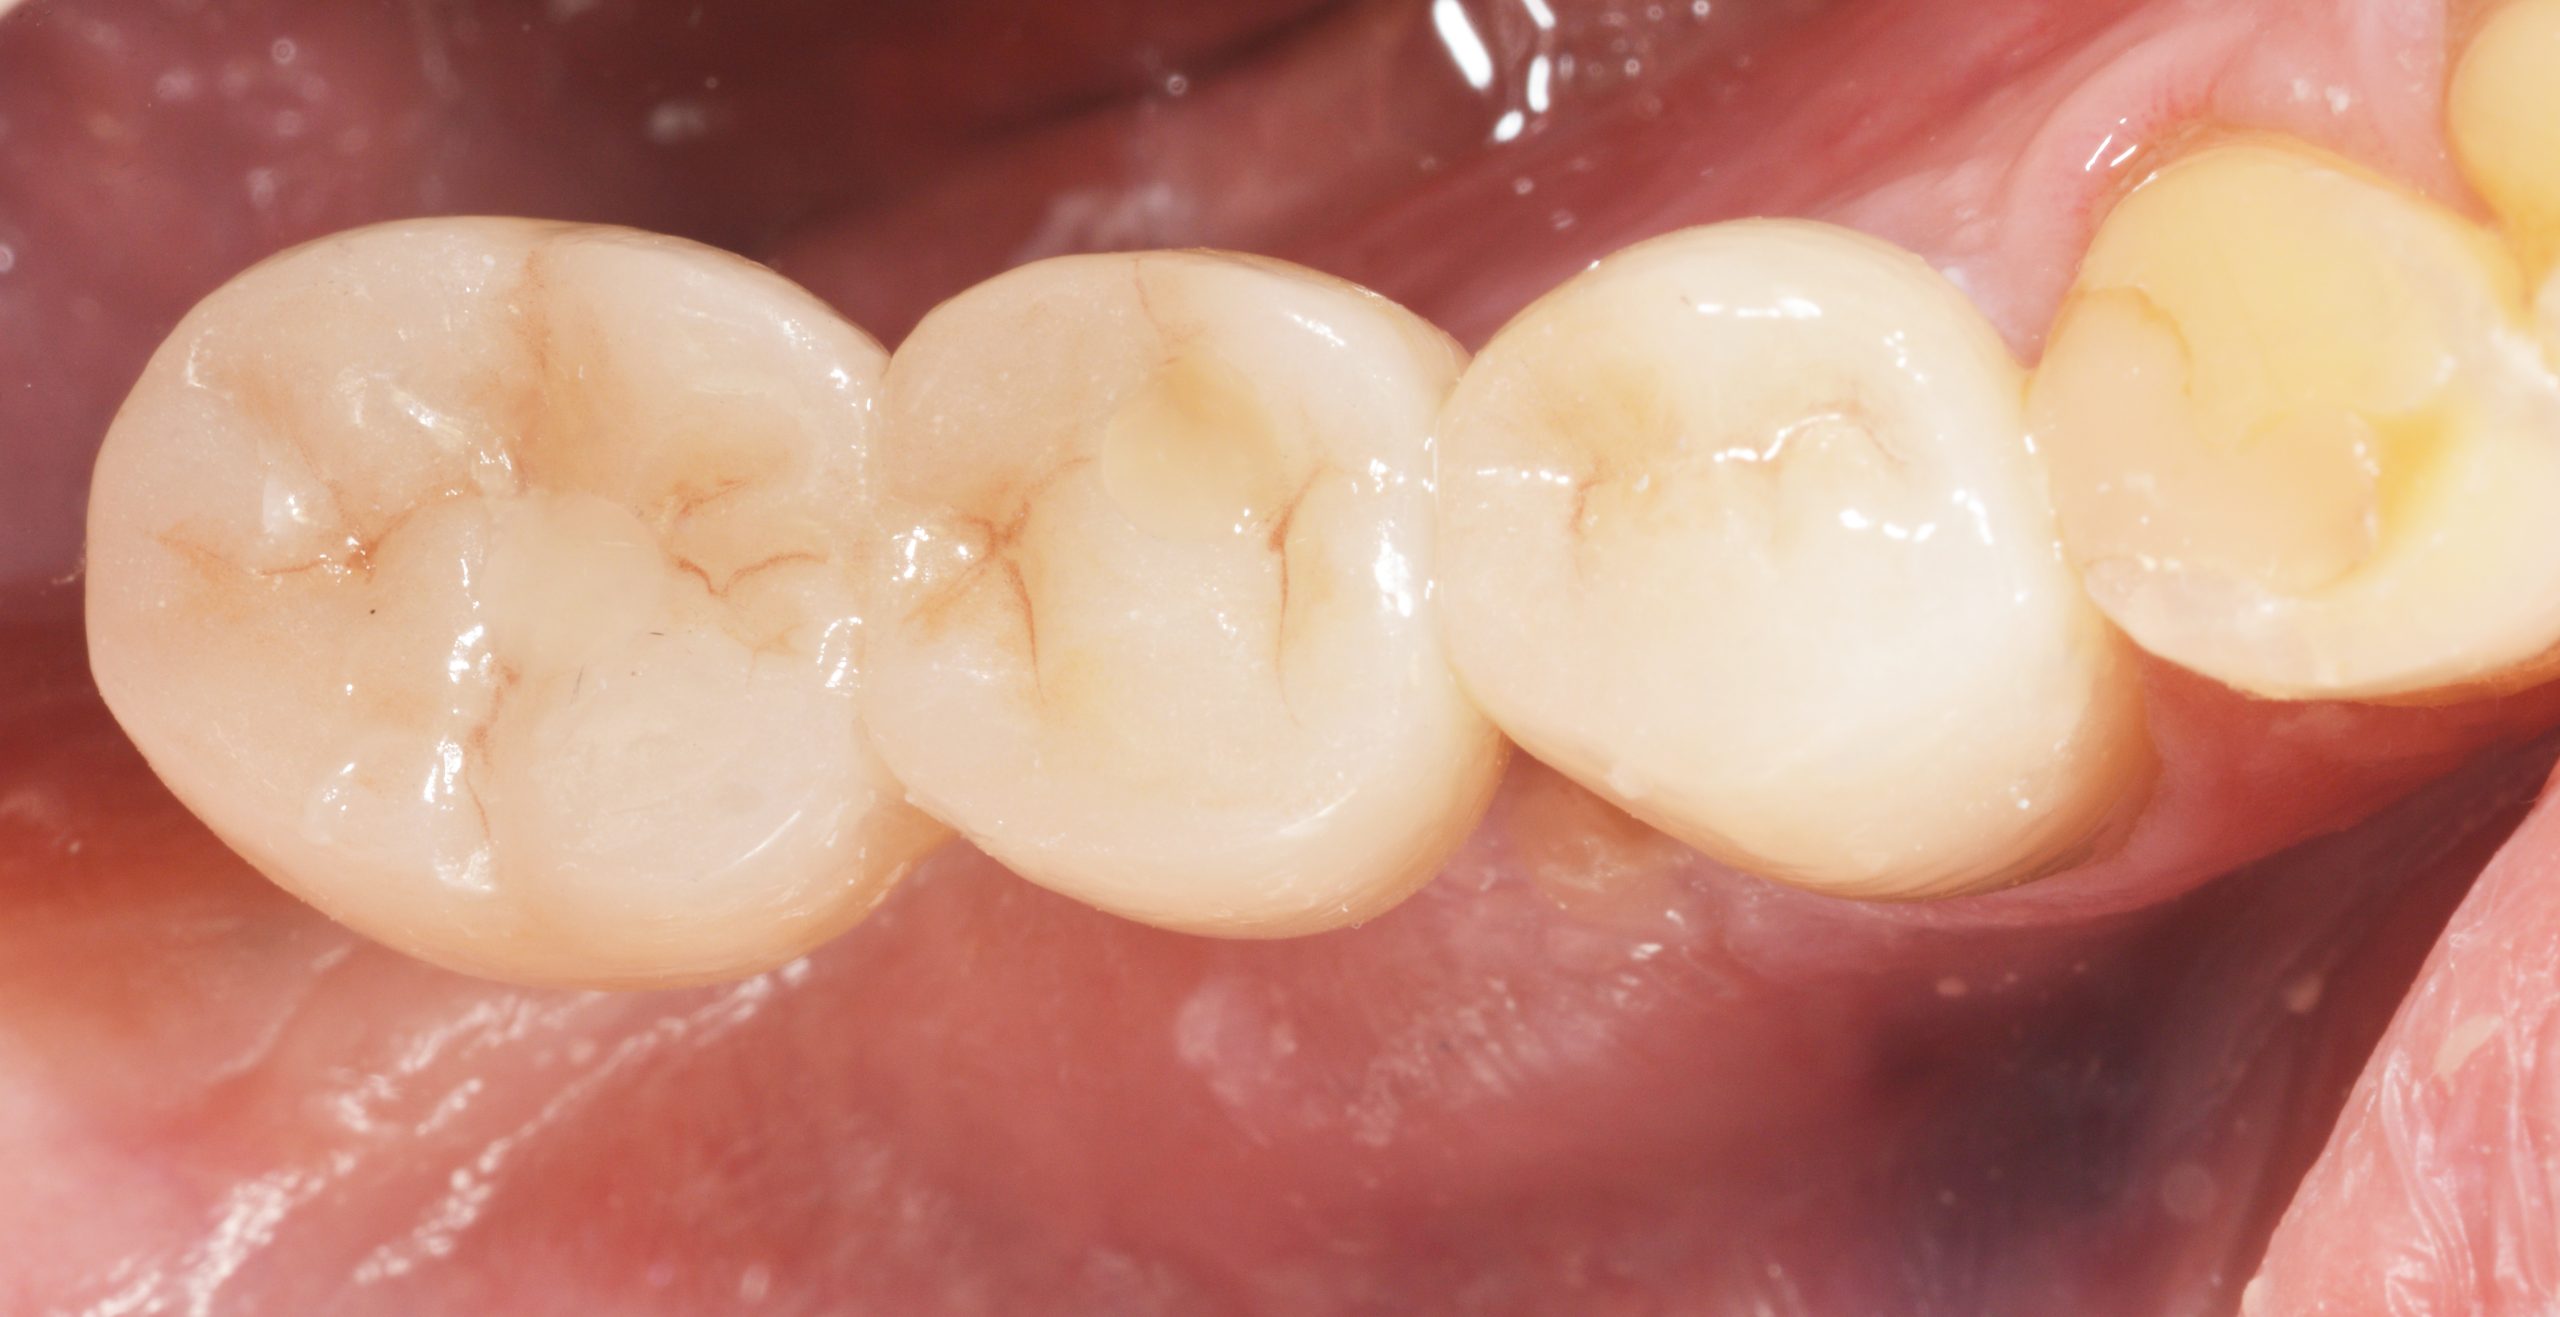

After the two abutments were tightened and filled over the screws, the ZrO2 block was bonded intraorally and the openings were then sealed with plastic material.

In addition, the dental technicians ensured a cleaning-friendly basal passage between 45 and 46. The handling of the interdental brushes was checked and the patient was instructed to attend a regular recall.

The X-ray 14 months later shows a stable peri-implant bone level, which may have increased distally to the 2.9 implant.